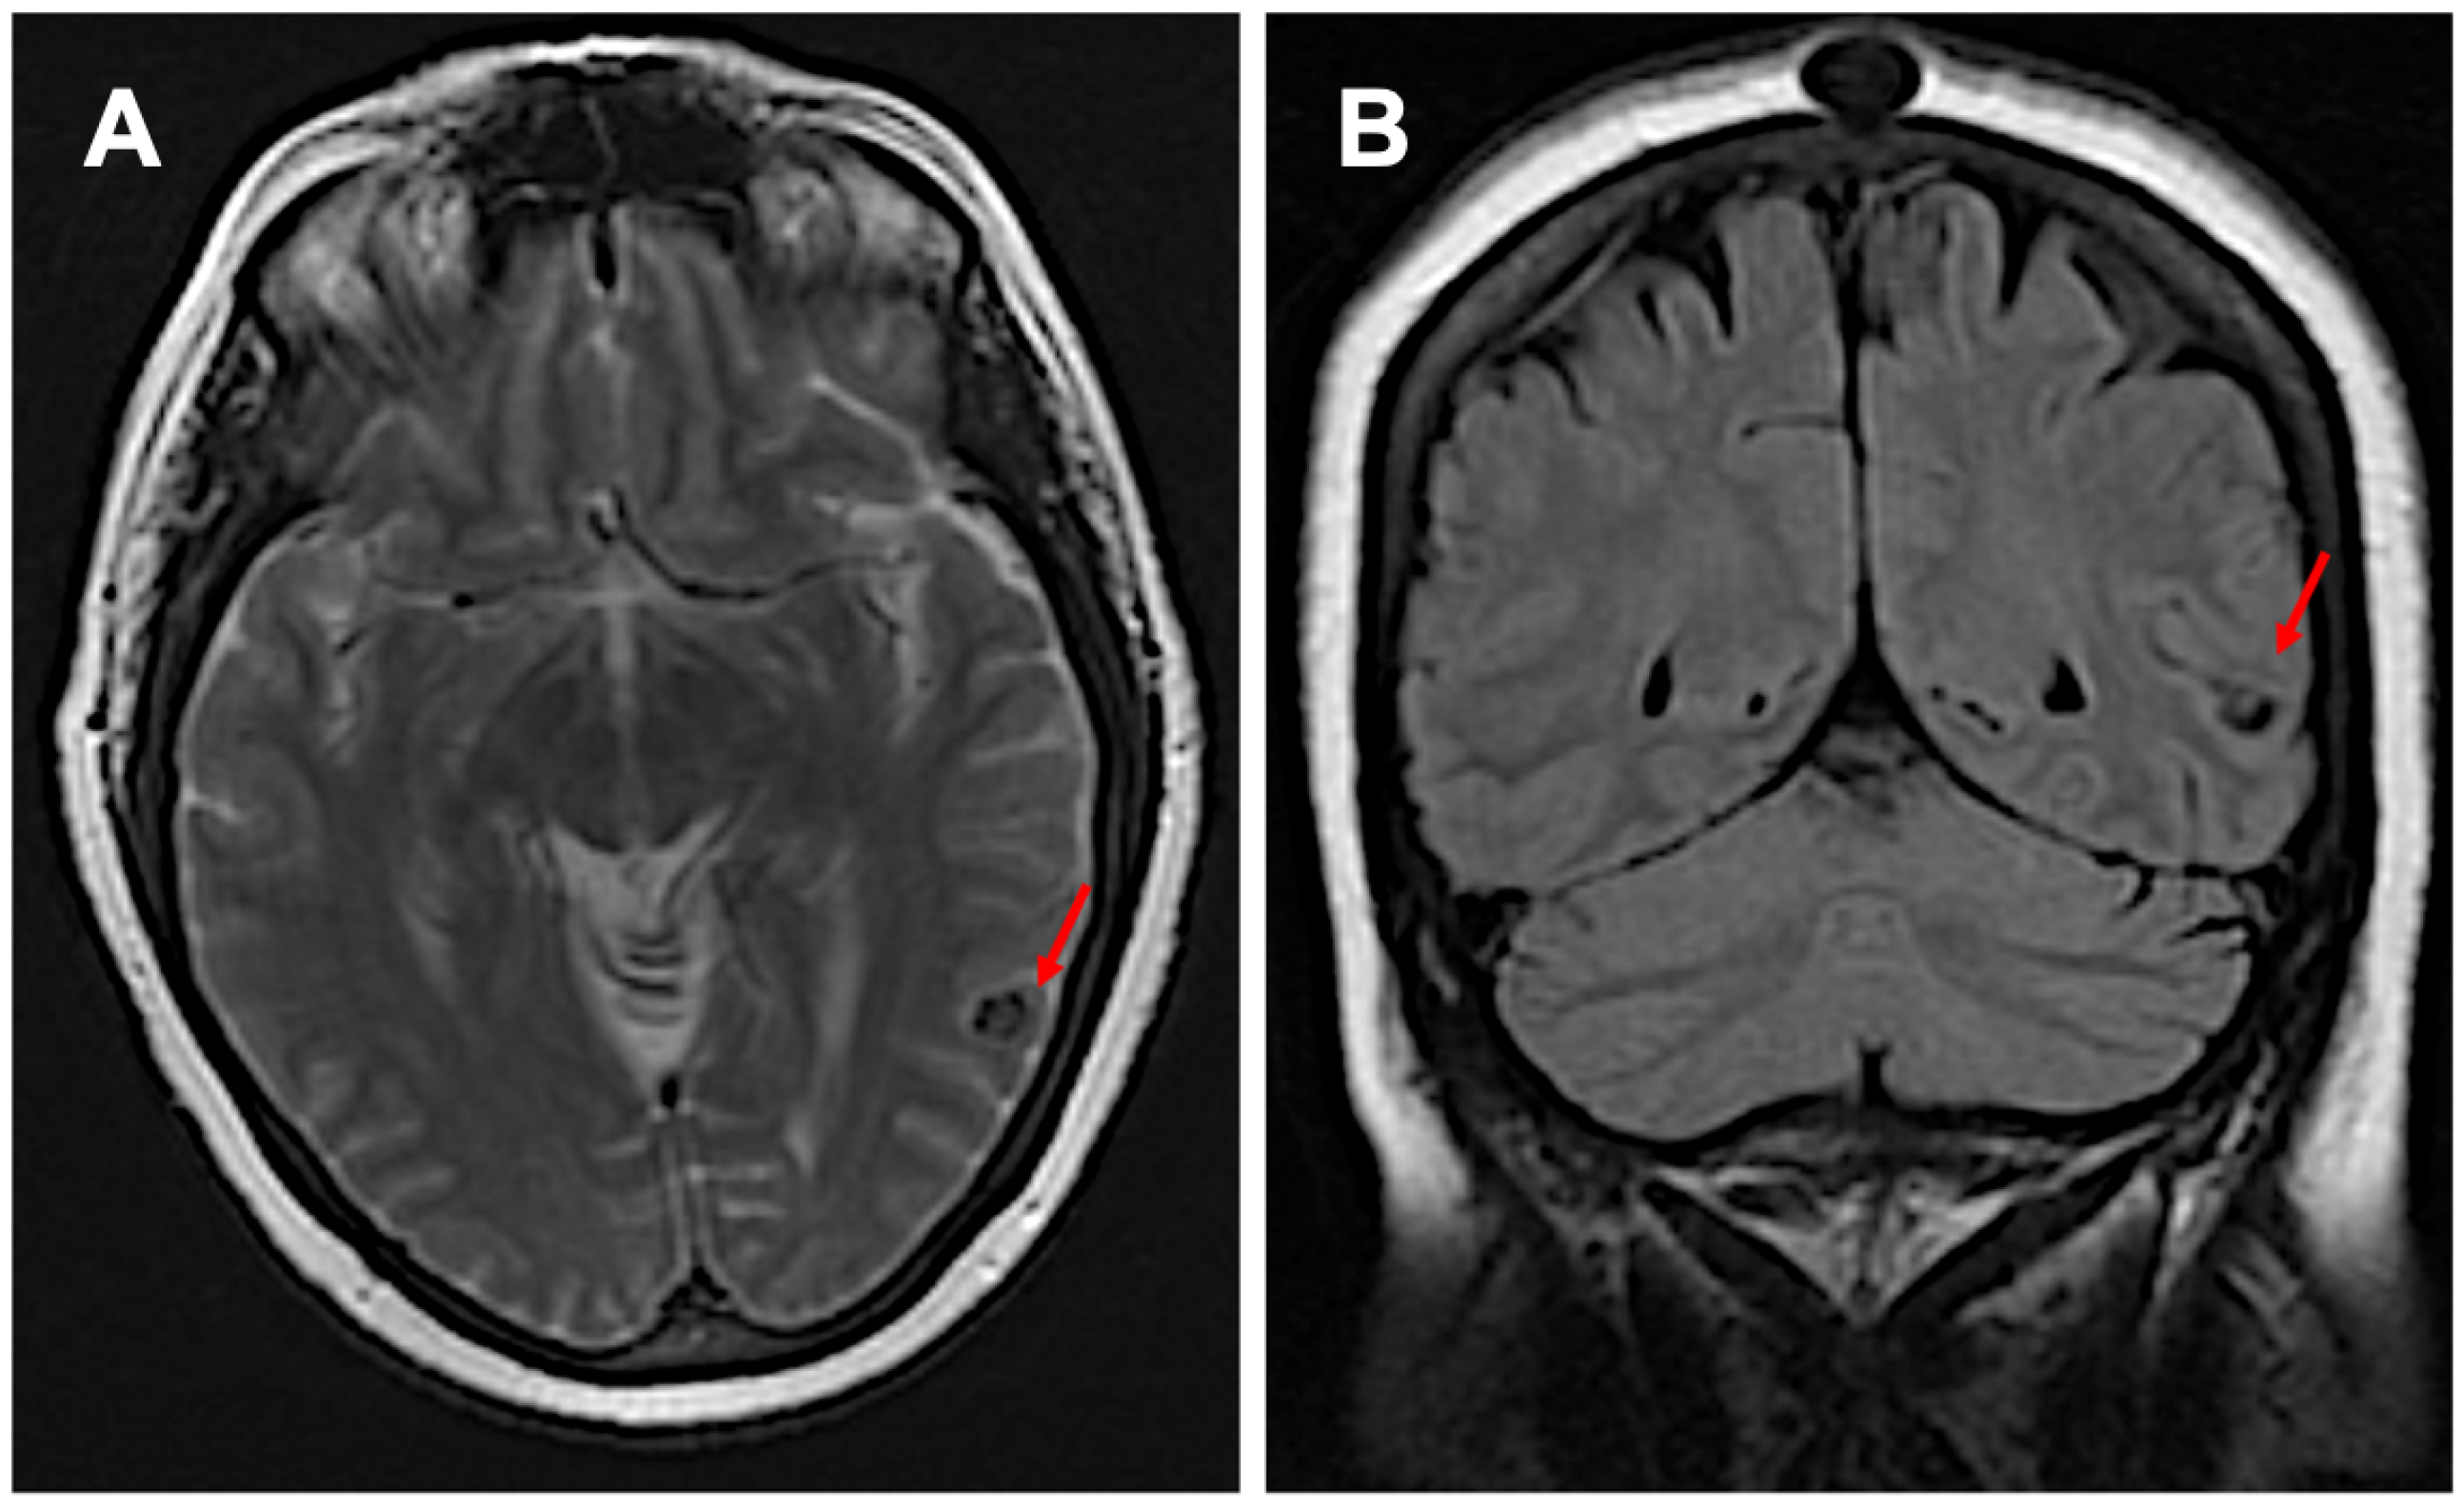

A 64-year-old Hispanic female presented with persistent anomic aphasia for several weeks, accompanied by intermittent occipital headaches and paresthesia in the left upper and lower extremities. She denied any motor deficits or other systemic symptoms. On examination, her vital signs were within normal limits except for elevated blood pressure (181/85 mmHg). Her past medical history was significant for NCC and obesity, diagnosed in 1996 after experiencing seizures following travel to the Dominican Republic, where she had consumed undercooked meat. Brain imaging at that time confirmed NCC, and she was treated with a single course of albendazole in 1998. Her seizures were well controlled with phenytoin and carbamazepine, later transitioning to levetiracetam for improved management. She had also undergone bariatric surgery in 2016 and had been receiving semaglutide for weight reduction therapy over the past six months. The initial laboratory workup, including inflammatory markers (Table 1), was largely unremarkable except for a positive enzyme-linked immunosorbent assay (ELISA) for TS. Brain imaging performed in 2024 revealed NCC reactivation, characterized by localized inflammation and cystic changes following semaglutide therapy [Figure 1]. Notably, prior brain imaging from 2021, before semaglutide initiation, had shown no evidence of active NCC [Figure 2].

Figure 2. Imaging before starting semaglutide: subpanel (A) shows inactive neurocysticercosis without surrounding edema in the transverse view, while subpanel (B) presents the coronal view (red arrows).